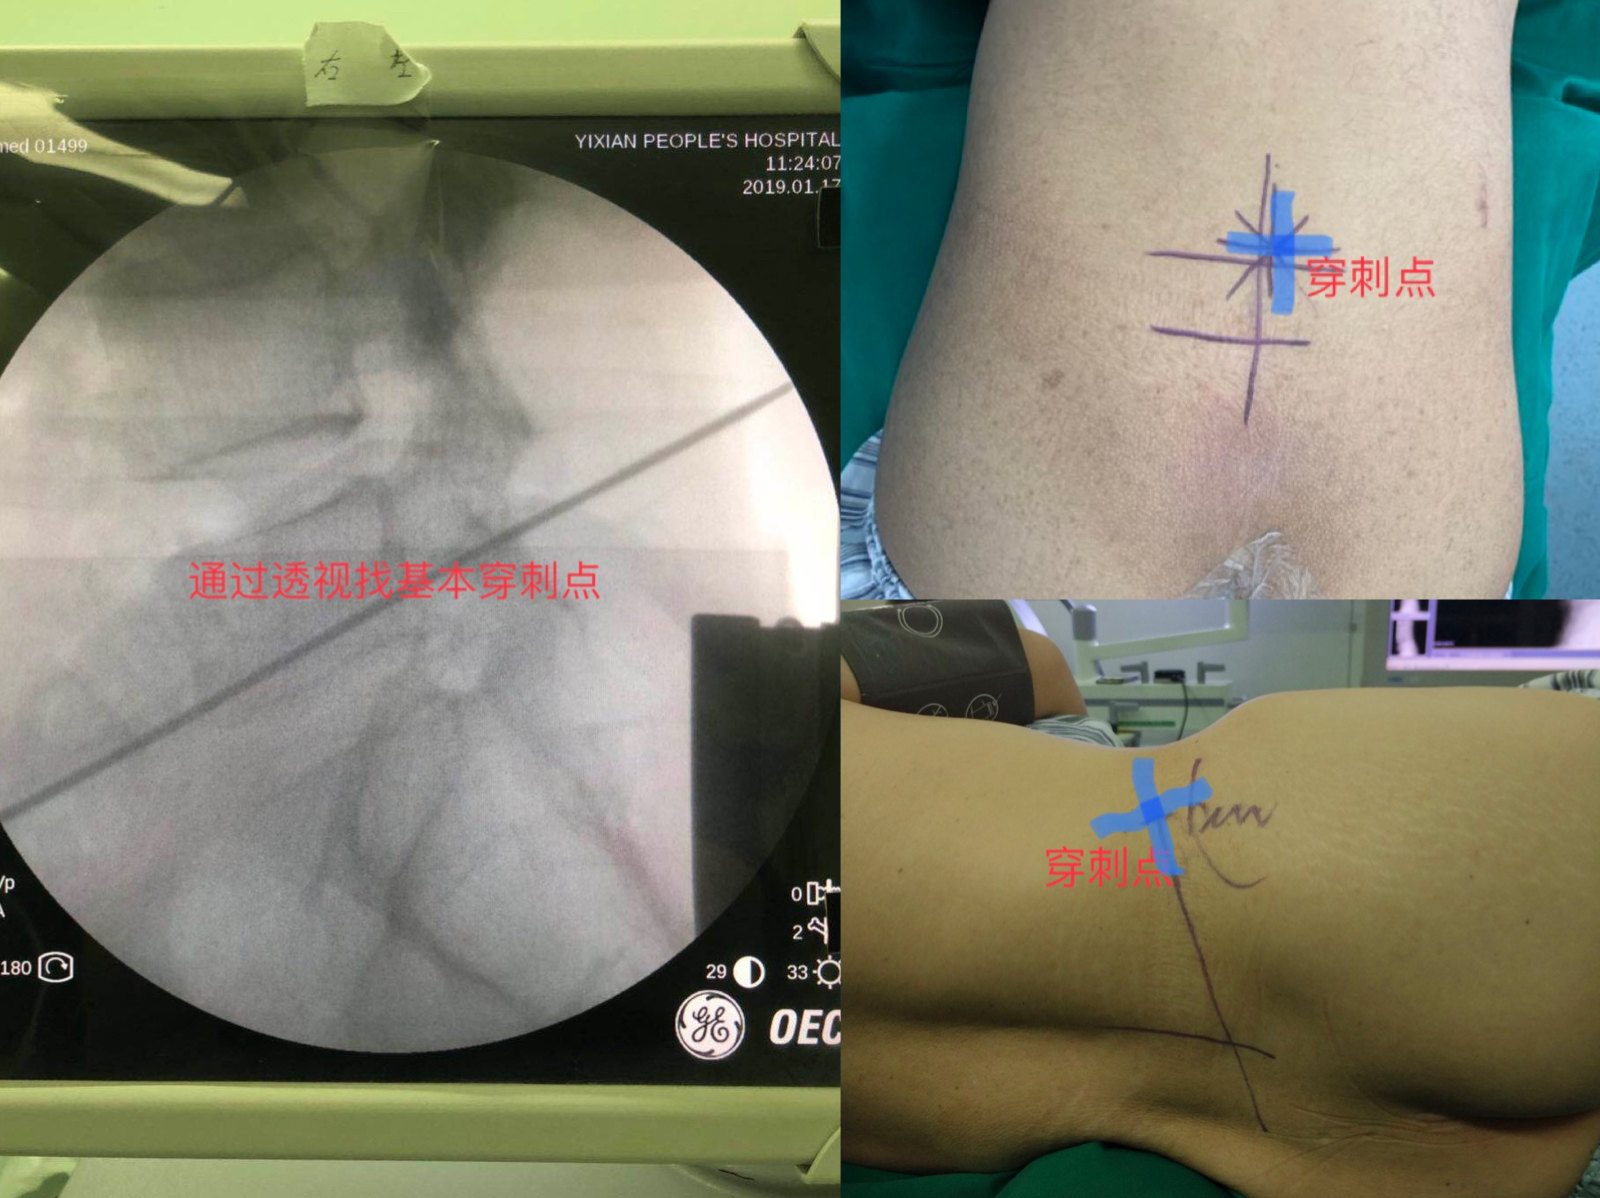

确定穿刺点

摆好体位后,我们会通过x线照射找到穿刺到达突出椎间盘的人体体表的进针点并标记好。